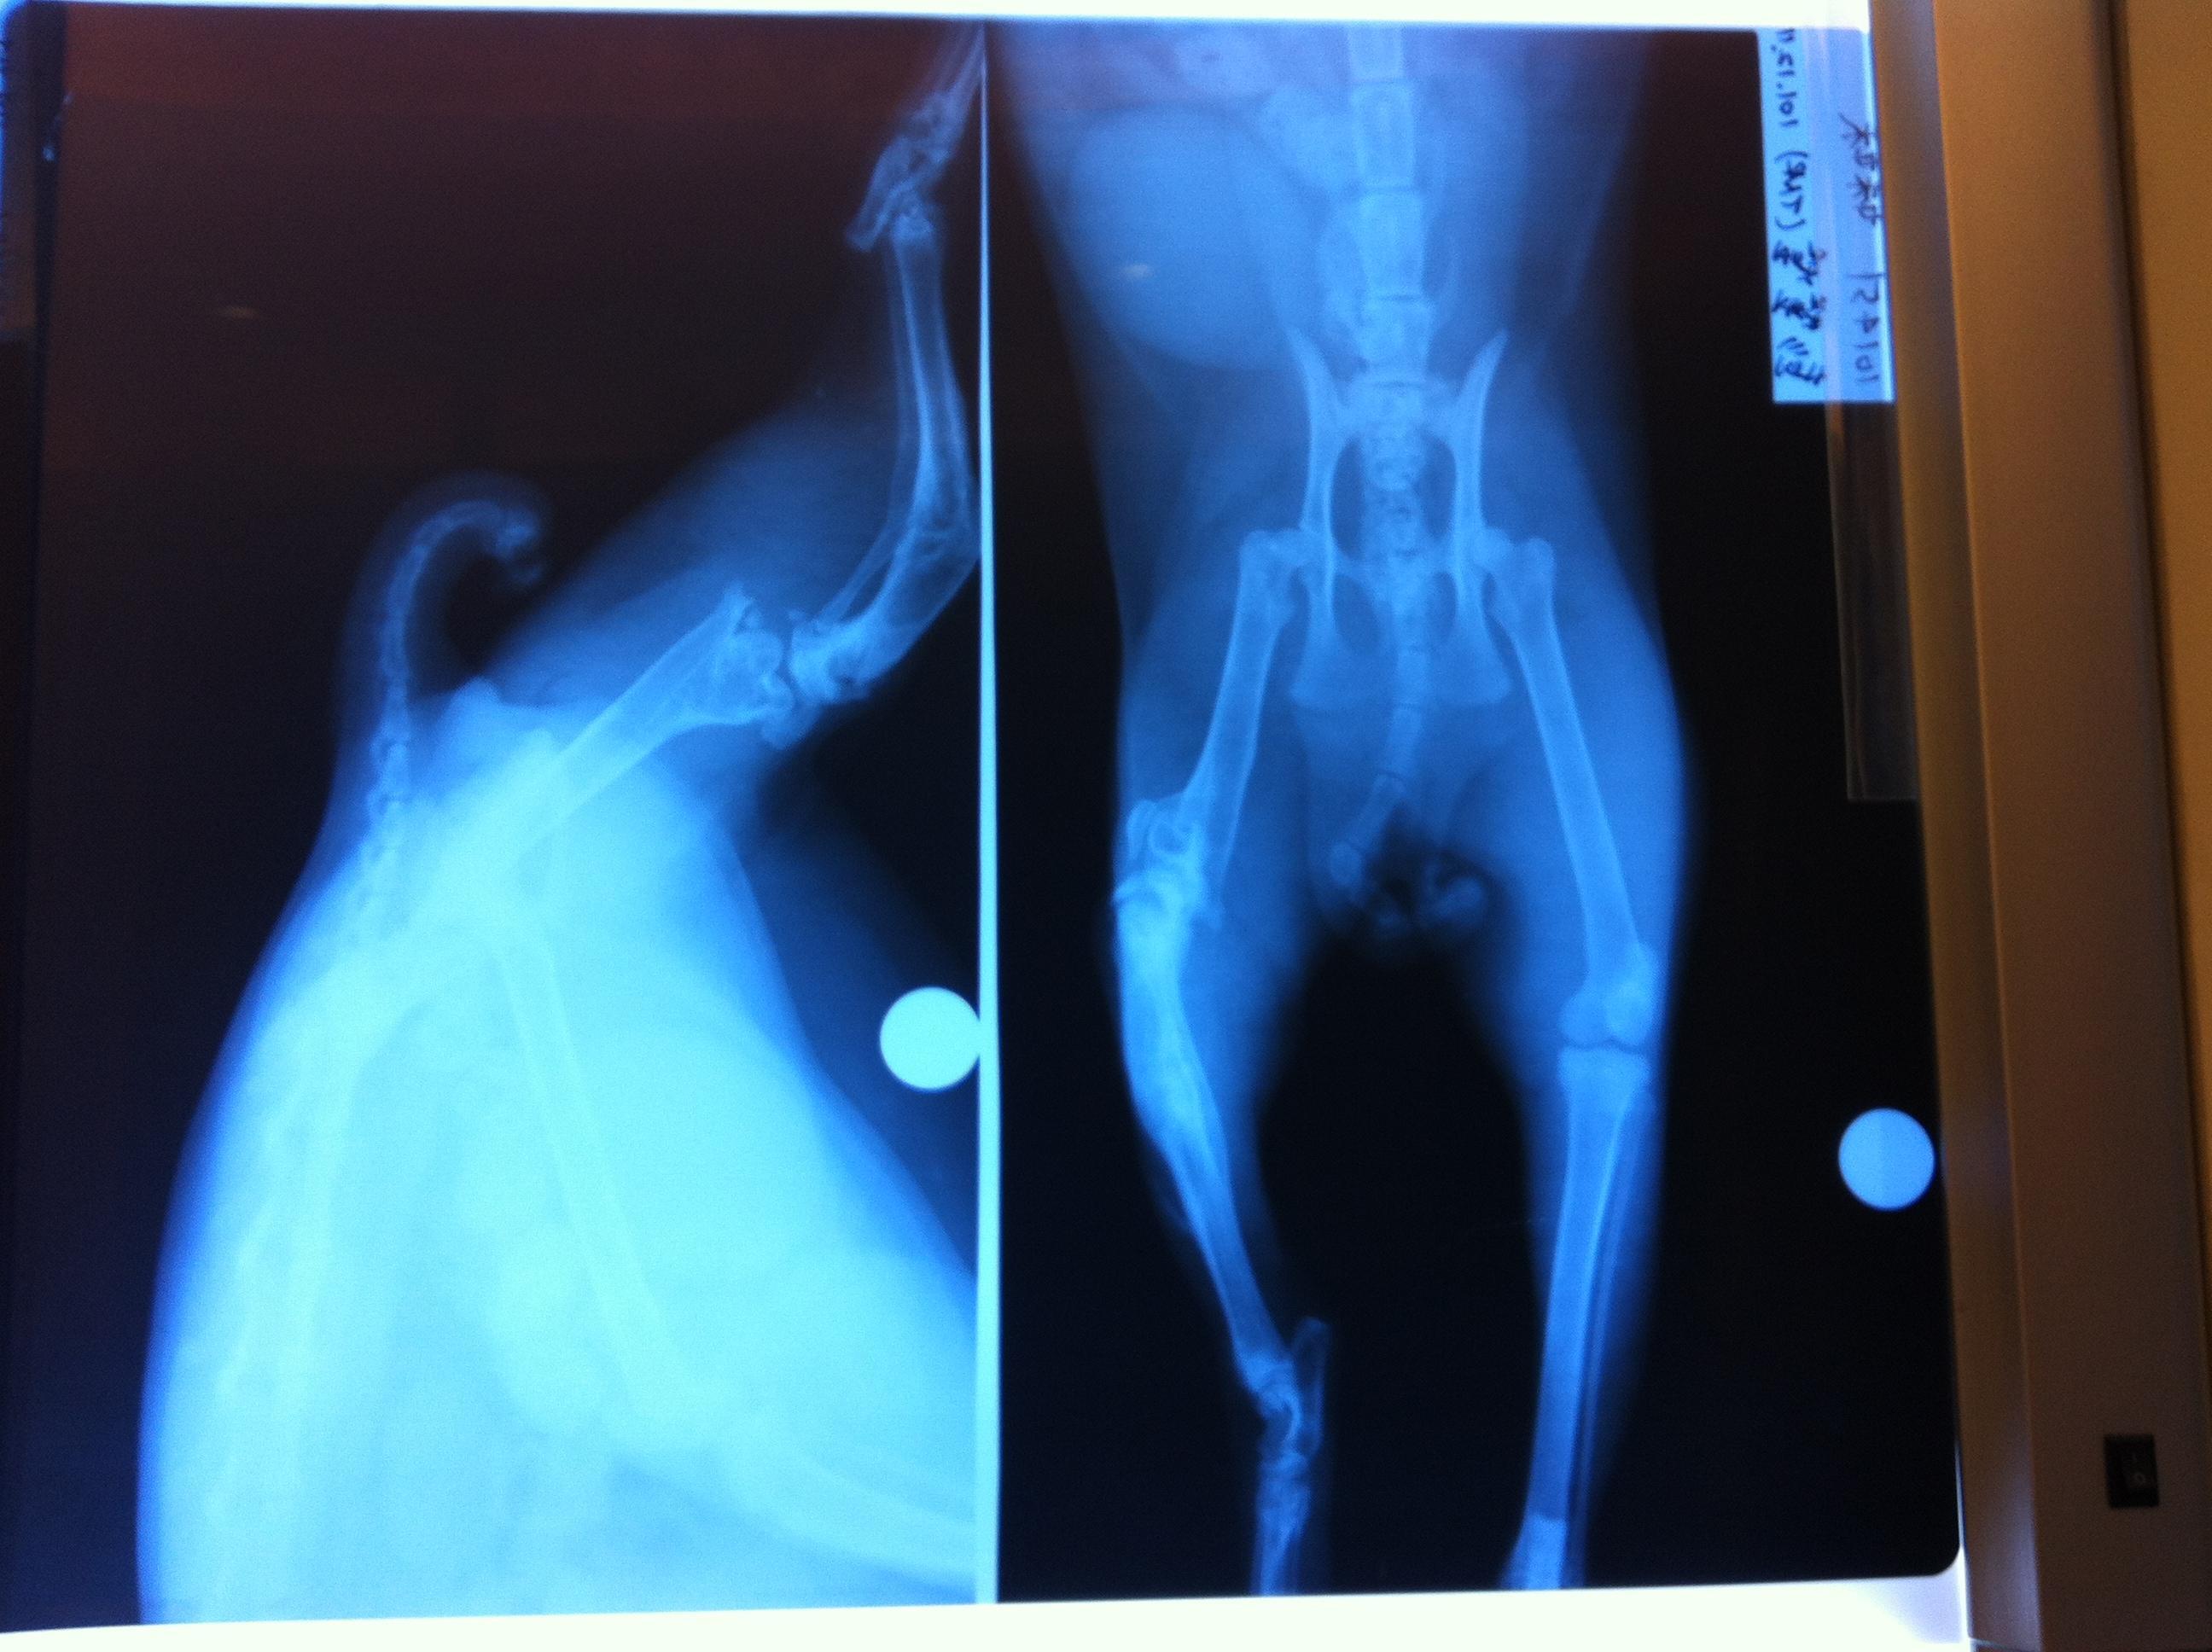

主題: 後腿二處斷裂的小橘妹妹 申請者姓名: 彭瑩瑩 花色: 申請日期: 2012-12-25 00:33:53 申請者部落格: 申請者臉書網址: 所在縣市/合作醫院: 桃園縣/思邁爾動物醫院 治療費用: 28000元 需求人數: 30人 已結案 (2013-08-06 13:45:45) 報名人員: Jerry(已付款)、May Chuang(已付款)、丁小丁(已付款)、Cherry Hsu(已付款)、Eli Tsao(已付款)、Eli Tsao(已付款)、游妃妃(已付款)、Ma Yi(已付款)、杜杜(已付款)、leezu(已付款)、Lin YC(已付款)、Eliza Chen(已付款)、Wanhua Chan(已付款)、Molly Cheng(已付款)、Doris Chen、Yu-Chen Lee(已付款)、miraai(已付款)、陳阿條(已付款)、Mia Wei(已付款)、存錢筒(已付款)、丁小乖(已付款)、周振禮(已付款)、Doris(已付款)、yin(已付款)、Andrea Lin(已付款)、Vickie(已付款)、Raymond Kuo(已付款)、田馨(已付款)、阿修(已付款)、Vozaponmi Cheer(已付款)、okina、Weirong(已付款)、 候補人員: 動物病情說明: 這隻橘妹妹是我在餵養的浪浪,受到不明外力的撞擊(疑似車禍)而造成後左腿的嚴重骨折:小腿和大腿都斷裂。

因為她非常膽小怕人,都是等我離開才敢出來吃大家剩下的,所以發現得很晚。等到發現時,她小腿的骨折已經自行接合,但卻是長成歪的,大腿骨則裂成尖刺,刺進她的肉裡,關節也因而裂開脫離,也就是說她每走一歩路就有尖在刺,可憐的孩子就這樣拖著傷腿痛了不知道多少個日子!

手術是為了把關節移回原處,削除尖銳的裂骨,並打鋼釘固定。現在小橘妹妹很努力地修養,等候復元,希望大家可以幫忙她的手術費用。